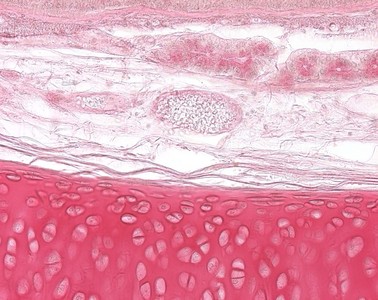

Präparat 6: Trachea (Affe), Querschnitt, H.-E.

Lamina propria mucosae, Trachea

untere Schicht der Tunica mucosa der Trachea aus lockerem Bindegewebe mit elatischen Netzen, die sich zu einer dichten Schicht, der Lamina fibrarum elasticarum, zusammenschließen. Sie enthält die seromukösen Glandulae tracheales.

Hyaliner Knorpel

makroskopisch bläulich- milchglasartig, kommt im Gelenkknorpel, am Ansatz der Rippen am Brustbein, in den Wachstumsfugen und in Trachea und großen Bronchien vor. Kollagen vom Typ II ist im hyalinen Knorpel vorherrschend. Die Kollagenfasern sind jedoch durch die Grundsubstanz maskiert und mit histologischen Routinefärbungen nicht darzustellen, sie sind jedoch mit dem Elektronenmikroskop sowie polarisationsmikroskopisch nachweisbar. Bei degenerativen Veränderungen können die Kollagenfasern "demaskiert" werden (sog. Asbestfaserung).

Im Bindegewebe der Lamina propria finden sich seromuköse Glandulae tracheales, deren Ausführungsgänge, zahlreiche Kapillaren, arterielle und venöse Blutgefäße und gelegentlich periphere Nerven. Auch sind an einigen Stellen Ansammlungen von Lymphozyten zu erkennen. Die Knorpelspangen (hyaliner Knorpel) der Tunica fibromusculocartilaginea werden von einem Perichondrium aus straffem kollagenen Bindegewebe umgeben.